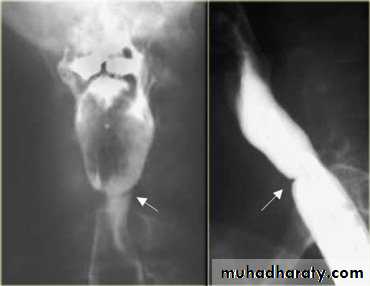

Sliding herniaOn the left initially, GE junction is below the esophageal hiatus. Later, stomach protrudes through hiatus

Para esophageal hernia

On the far left gas filled gastric funds (asterisk) protrudes through hiatus but GE junction (arrow) is below diaphragm